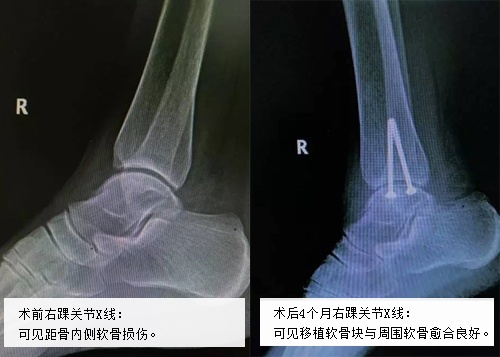

2016年10月8日,国庆假期结束后的第一天,吴阿姨又来到这里。“感谢王主任精湛的技术,我现在左踝关节感觉非常好,也不疼了。我这次来想让你们看看我的右踝关节,最近这俩月它一直疼,什么方法都试了可还是不缓解,想让主任你们也通过手术解决我的右踝关节问题。”吴阿姨向该科贺自克大夫解释。 王上增教授看了吴阿姨右踝关节的片子后,表示:“患者右踝关节疼痛的原因也是距骨软骨坏死,但与左侧不同的是右踝关节的稳定好,可以采用和左踝相同的手术方式来治疗,只不过不用重建外侧副韧带了,这样手术就相对简单很多了。” 就这样,在王上增教授及科室团队的共同协作下,吴阿姨的右踝也成功完成“关节镜辅助下距骨坏死清理并踝关节软骨移植术”。